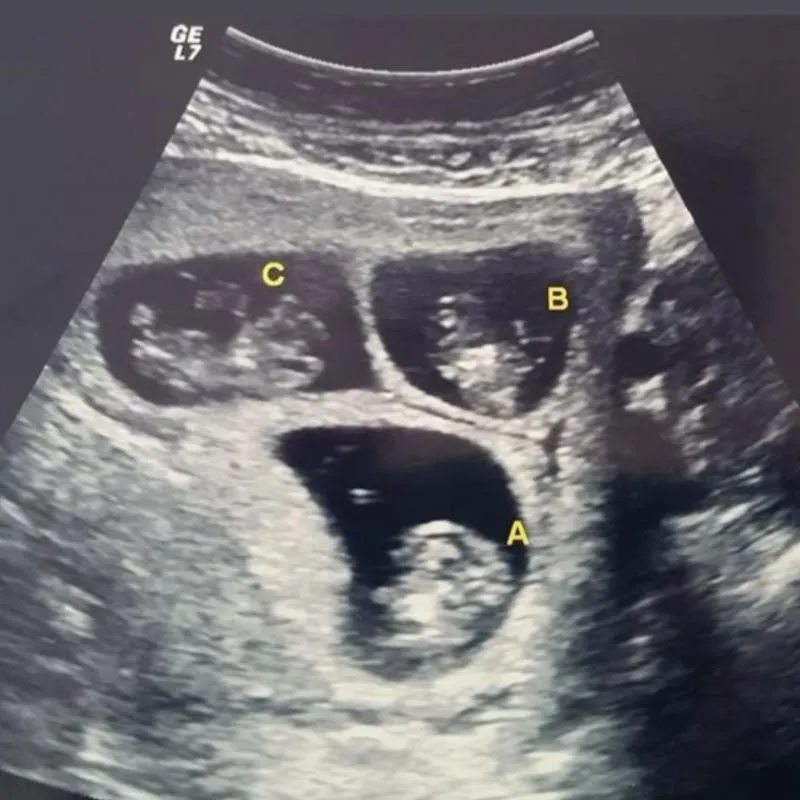

Essa ação é para ajudar uma mãezinha que está esperando Trigêmeos, de uma família muito simples.